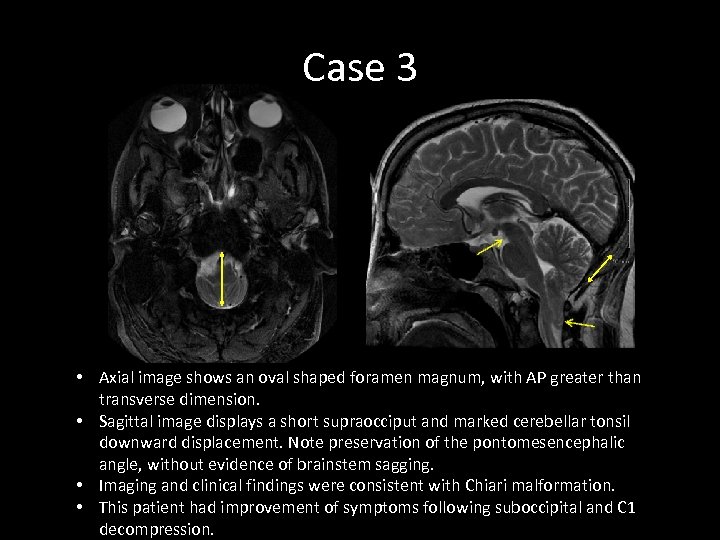

Case 3 • Axial image shows an oval shaped foramen magnum, with AP greater than transverse dimension. • Sagittal image displays a short supraocciput and marked cerebellar tonsil downward displacement. Note preservation of the pontomesencephalic angle, without evidence of brainstem sagging. • Imaging and clinical findings were consistent with Chiari malformation. • This patient had improvement of symptoms following suboccipital and C 1 decompression.

Case 3 • Axial image shows an oval shaped foramen magnum, with AP greater than transverse dimension. • Sagittal image displays a short supraocciput and marked cerebellar tonsil downward displacement. Note preservation of the pontomesencephalic angle, without evidence of brainstem sagging. • Imaging and clinical findings were consistent with Chiari malformation. • This patient had improvement of symptoms following suboccipital and C 1 decompression.